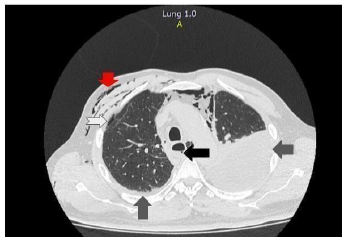

Al siguiente día, se remitió a institución de tercer nivel donde ingresó con soporte de oxígeno por máscara de no reinhalación a 10 litros y se realizó reacción en cadena de la polimerasa (PCR) para SARS-COV-2 con resultado positivo. Ante el cuadro clínico y paraclínicos tomados que indicaban alta sospecha de SB secundario a neumonía por COVID-19 y, teniendo en cuenta el compromiso hemodinámico del paciente dado por hipotensión sostenida a pesar de reanimación hídrica adecuada, se decidió realizar una tomografía axial computarizada de tórax de alta resolución (TACAR) que confirmó perforación esofágica en el tercio distal anterolateral izquierdo con engrosamiento de las paredes esofágicas proximal a zona de perforación y derrame pleural bilateral (ver Figura 1).

Figura 1 TACAR tórax. Flecha negra: perforación esofágica del lado izquierdo. Flechas grises: derrame pleural bilateral. Flecha blanca: neumomediastino. Flecha roja: enfisema del tejido celular subcutáneo.